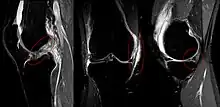

The unhappy triad, also known as a blown knee among other names, is an injury to the anterior cruciate ligament, medial collateral ligament, and meniscus. Analysis during the 1990s indicated that this 'classic' O'Donoghue triad is actually an unusual clinical entity among athletes with knee injuries. Some authors mistakenly believe that in this type of injury, "combined anterior cruciate and medial collateral ligament (ACL- MCL) disruptions that were incurred during athletic endeavors" always present with concomitant medial meniscus injury. However, the 1990 analysis showed that lateral meniscus tears are more common than medial meniscus tears in conjunction with sprains of the ACL.[1]

The unhappy triad occurs due to a lateral blow to the knee causing a rupture in the anterior cruciate ligament, medial collateral ligament, and meniscus. Injury is most often sustained when a lateral (from the outside) force impacts the knee while the foot is fixed on the ground. The strong valgus or rotary force to the knee tears the ACL, MCL, and medial meniscus all together. This type of injury occurs often in contact sports such as football, rugby, or motocross. During the injury, the leg is laterally rotated and over-abducted. In about 10% of cases, the force is applied to the opposite side of the knee, and the lateral and posterolateral ligaments are torn.

The classic O'Donoghue triad is characterized by an injury to three knee structures (in order):

- the anterior cruciate ligament

- the medial meniscus (however, lateral meniscus[1] injuries are more commonly seen among athletes, leading to the definition of the O'Donoghue triad most commonly used today.) [3][4][5]

- the medial collateral ligament (or "tibial collateral ligament")

Injury to the medial meniscus is about five times greater than injury to the lateral meniscus due to its anatomical attachment to the MCL.[8] Lateral meniscal tears are more common in acute ACL injuries, whereas medial meniscal injuries are more common in chronic ACL-deficient knees and more amenable to repair.[9]

Meta-analysis shows that in acute injuries of the ACL associated with a meniscus tear, 44% were of the medial meniscus, whereas 56% were of the lateral meniscus; in chronic ACL insufficiency, 70% were medial whereas 30% were lateral.[10]

A study containing 100 consecutive patients with a recent anterior cruciate ligament injury were examined with respect to type of sports activity that caused the injury. Of the 100 consecutive ACL injuries, there were also 53 medial collateral ligament injuries, 12 medial, 35 lateral and 11 bicompartmental meniscal lesions. 59/100 patients were injured during contact sports, 30/100 in downhill skiing and 11/100 in other recreational activities, traffic accidents or at work.[13]

An associated medial collateral ligament tear was more common in skiing (22/30) than during contact sports (23/59), whereas a bicompartmental meniscal lesion was found more frequently in contact sports (9/59) than in skiing (0/30). Weightbearing was reported by 56/59 of the patients with contact sports injuries whereas 8/30 of those with skiing injuries. Non-weightbearing in the injury situation led to the same rate of MCL tears (18/28) as weightbearing (35/72) but significantly more intact menisci (19/28 vs 23/72). Thus, contact sports injuries were more often sustained during weightbearing, with a resultant joint compression of both femuro-tibial compartments as shown by the higher incidence of bicompartmental meniscal lesions. The classic "unhappy triad" was a rare finding (8/100) and Fridén T, Erlandsson T, Zätterström R, Lindstrand A, and Moritz U. suggest that this entity should be replaced by the "unhappy compression injury".[13]

In 1936, Cambell stated that an "impairment of the anterior crucial and medial ligaments is associated with injuries of the internal cartilage". In 1950, O'Donoghue described the unhappy triad as: (1) rupture of the medial collateral ligament, (2) damage to the medial meniscus and (3) rupture of the anterior cruciate ligament. O'Donoghue estimated the incidence rate in the traumatic sports knee to be 25%.[3]

In 1991, Shelbourne and Nitz questioned the validity of O'Donoghue's terrible triad study. A review of all arthroscopically confirmed acute injuries of second degree or worse to the ACL and MCL was performed. Of the 52 knees reviewed, 80% of group 1 had lateral meniscus tears and 29% had associated medial meniscus tears. None of the medial meniscus tears were isolated; medial meniscus tears were not present in the absence of a lateral meniscus tear.[3] From this study, it was concluded that the structures more typically involved in a triad were the anterior cruciate ligament, medial collateral ligament, and the lateral (not medial) meniscus.